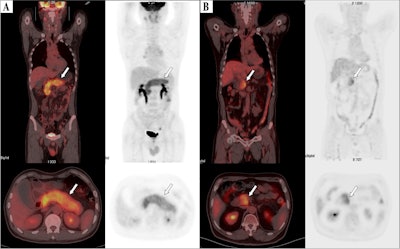

F-18 FDG-PET/CT images of patients. (A) Image of a 61-year-old male patient with type 1 autoimmune pancreatitis (AIP) demonstrating diffuse enlargement of the pancreas (arrows). The serum IgG4 level was 2,260.0 mg/dL, and the TLG2.5 was 413.8 g/ml×cm3. According to the nomogram, his relapse probability is more than 95%. The patient discontinued steroid use during the maintenance phase, and 7 months later, he relapsed, with imaging showing diffuse re-enlargement of the pancreas. (B) Image of a 60-year-old male patient with type 1 AIP, showing focal enlargement in the head of the pancreas (arrows). The serum IgG4 level was 980 mg/dL, and the TLG2.5 was 92.7.0 g/ml×cm3. According to the nomogram, the patient’s relapse probability is less than 50%. After symptom relief, the patient did not receive maintenance treatment, and has been followed up for 4 years without relapse. Image courtesy of BMC Gastroenterology.